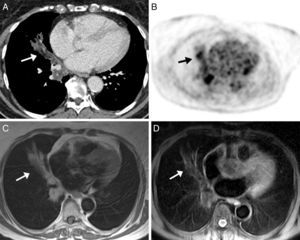

Dados los antecedentes oncológicos de la paciente, se decidió realizar una tomografía por emisión de positrones (PET)/TC. En el componente PET del estudio se observaron áreas hipermetabólicas en las zonas de consolidación pulmonar. En el componente de TC se objetivó la presencia de opacidades parenquimatosas con atenuación grasa, emitiéndose el diagnóstico de presunción de neumonía lipoidea. Debido a que la paciente rehusaba realizarse una fibrobroncoscopia, se optó por ampliar el estudio de la opacidad mediante RM de tórax, en la que se evidenciaron zonas hiperintensas en secuencias potenciadas en T1, que se suprimían en secuencias con supresión grasa (por ejemplo, la secuencia STIR) (fig. 2). Estos hallazgos eran compatibles con NLE.

Imagen axial de TC de tórax en ventana de mediastino (A) en la que se observa una opacidad en pulmón derecho de distribución peribronquial, con áreas de atenuación grasa (flecha). Imagen de PET (B) en la que se observan áreas hipermetabólicas en la base pulmonar derecha, coincidiendo con las opacidades visualizadas en TC (flecha). Imágenes axiales de RM, en la que se demuestra hiperintensidad de señal de la opacidad en secuencias potenciadas en T1 (C) y supresión de su señal en secuencia de saturación grasa (D) (flechas).